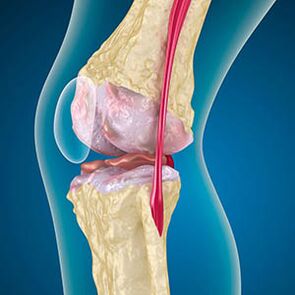

W przypadku artrozy chrząstka wyściełającą krawędzie kości jest ścieranie lub całkowicie nieobecna. Uszkodzona tkanka nie jest źródłem bólu, ponieważ nie ma receptorów. Zapalenie w pobliskich strukturach powoduje charakterystyczne objawy.

Ciało kontynuuje regenerację uszkodzonych tkanek, ale chrząstka rośnie nierównomiernie. W rezultacie powstają nieprawidłowości, które zranią inne elementy stawu. Naturę osteofitów tłumaczy się odszkodowaniem w sprawie gładkiej chrząstki stawowej. Inna wersja wskazuje, że wzrost „ostrogów” Jest to związane z próbą ustabilizowania stawu przyśrodkowego lub bocznego z powodu osłabienia mięśni.

Jaka jest przewlekła artroza stawu kolanowego? Ból występuje w ścięgnach i więzadłach tylko wtedy, gdy siły mięśni przestają trzymać kości i je kontrolować. Dlatego wyróżnia się biomechaniczne przyczyny bólu i artrozy: